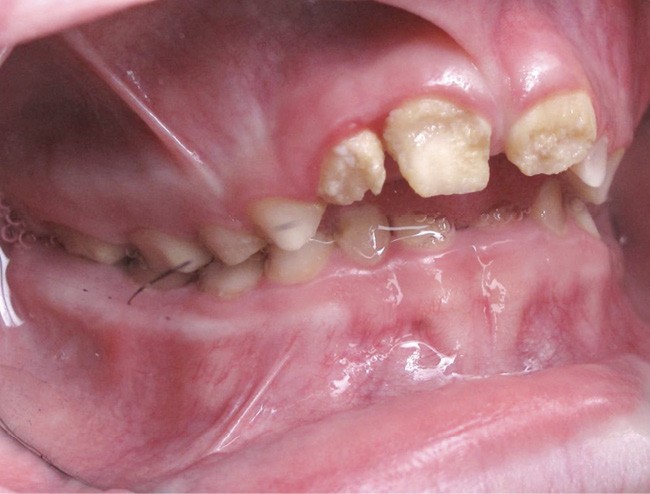

Il existe des anomalies dentaires (tabl. I) [1-12], mais aussi occlusales associées aux AI (fig. 1 et 2).

Selon de nombreuses études, l’anomalie occlusale la plus fréquemment retrouvée en association avec les AI est l’infraclusion antérieure, puisqu’elle est retrouvée chez 22 à 64 % des patients présentant cette affection, et encore plus chez les femmes [2,8,13-19]. Cette anomalie touche tous les types d’AI mais à des degrés très divers. Son incidence semble élevée dans les formes hypominéralisées, moindre dans les formes hypoplasiques et nettement moindre dans les formes hypomatures [8,17,18]. La sévérité de l’atteinte amélaire ne semble pas corrélée avec la présence ou l’intensité de cette malocclusion [17].